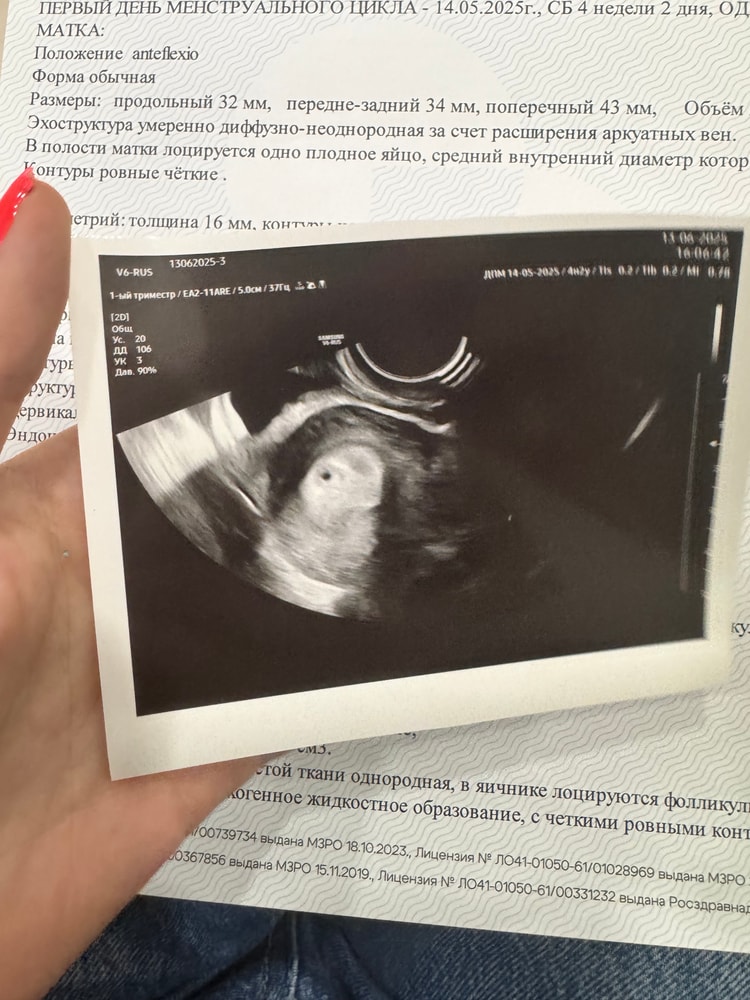

Сходила на узи, к вечеру похоже хгч поднялся, все , это не биохимическая, а маточная беременность малого срока 🥰😍Угрозы и прочую лабуду опровергли ☺️❤️